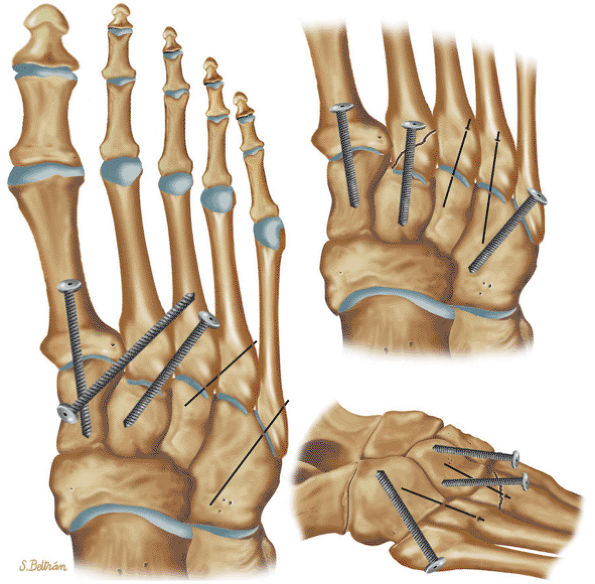

to determine whether there is enough bone to permit healing, if reattachment with absorbable pins, Kirschner wires, or screws is undertaken. Primary chondral lesions without attached bone are excised, with débridement and drilling or abrading of the base. Loose fragments are either fixed with absorbable pins, Kirschner wires, or screws or are excised with drilling of the base. Displaced lesions are excised, and the base is drilled or abraded if it cannot be reattached.